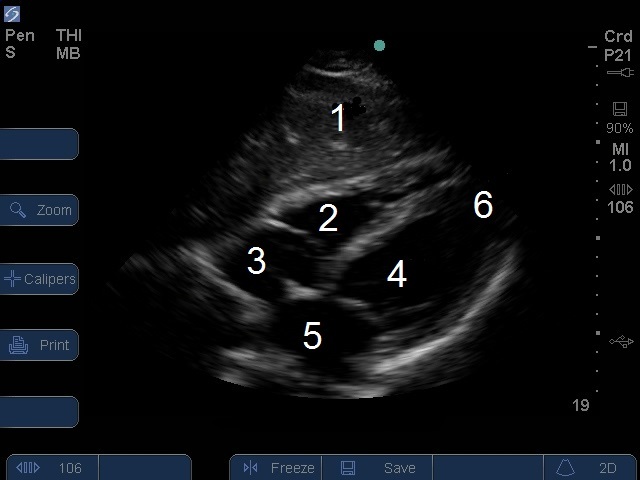

S Series : Image - Vue sous-xiphoïdienne du cœur

1. Foie

2. Ventricule droit (VD)

3. Oreillette droite (RA)

4. Ventricule gauche (VG)

5. • Oreillette gauche (OG)

6. Apex cardiaque